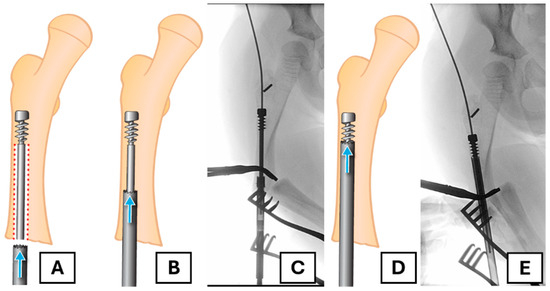

Given that the female component had migrated distally, we were left with two choices for retrieving it: antegrade through the greater trochanter or retrograde through the fracture. We recommend removing it retrogradely to prevent excessive bone loss in the proximal area, which could prevent solid fixation of the new implant. The anchoring of the revision rod in the greater trochanter is potentially compromised with the antegrade removal of this bone (Figure 1B,C).

In pre-operative planning, we considered several approaches to retrieval. Retrograde retrieval of the rod is possible if a guidewire can be passed into the rod from a proximal entry point; however, reaming over the guidewire would likely result in significant bone loss around the greater trochanter, sacrificing the potential remaining bone for revision fixation (Figure 1). We could consider leaving the existing rod in situ and bypassing it with a second rod, but it may prove challenging and would likely complicate any future exchange. Creating a clamshell osteotomy or another osteotomy at the level of the proximal fixation could allow for retrograde extraction, but the technique would involve more significant soft tissue stripping or the creation of a second fracture site. Lastly, although a retrograde telescopic nail technique has recently shown a promising result and might be another choice for revision [7]. We prefer not to use the method as it entails performing arthrotomy of the knee, which we would like to avoid.

Figure 1. (A) Intra-operative femoral radiograph showing distal migration of the female component into the medullary canal, with associated rod failure and fracture. (B) Illustration of the predicted bone loss (yellow and red shaded area) with a traditional antegrade removal. This red area highlights the critical bone at the greater trochanter apophysis, which is required for secure fixation. (C) Illustration showing how antegrade removal compromises the fixation of a new FD rod, as the threads of the female component would be placed in an area of bone loss (red shaded). (D) Intra-operative radiograph showing the placement of the new FD rod; the female threads are in the red shaded area (yellow arrow), which will compromise a fixation with the traditional removal method.